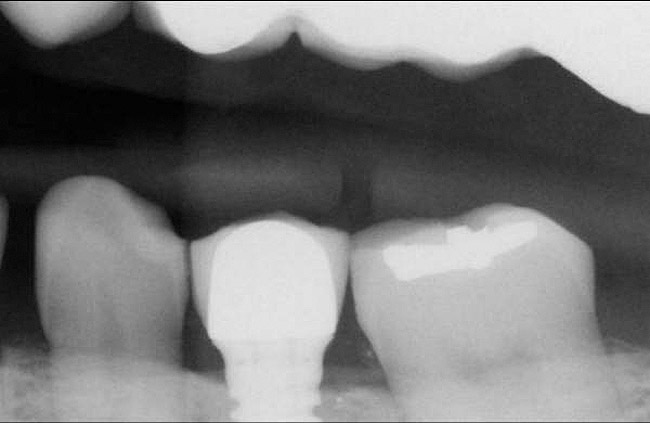

Horzontal Components of Implant Placement

The horizontal aspect of implant spacing is critical to avoid bone loss on adjacent teeth or implants. Single-tooth implants should be placed 1.5 mm to 2 mm from the adjacent teeth,19,20 and implants should have at least 3 mm of space between them21 (Figure 12). By keeping a minimum 1.5-mm distance from the adjacent tooth and a minimum distance of 3 mm between adjacent implants, angular defects resulting from crestal bone remodeling can be kept from becoming horizontal defects19-22 (Figure 13). This distance allows the bone on the adjacent tooth to stay at its current level. Conversely, if bone loss on the adjacent tooth or implant occurs, the bone loss will not affect the adjacent tooth or implant. This is especially critical in the anterior regions of the mouth where papilla height is more important for an esthetic result.23-27

Figure 12  Horizontal spacing needed between the natural tooth and the implants and between the adjacent implants.

Figure 12

Figure 13  Radiograph depicting the necessity of horizontal placement parameters to prevent vertical defects from becoming horizontal defects.

Figure 13